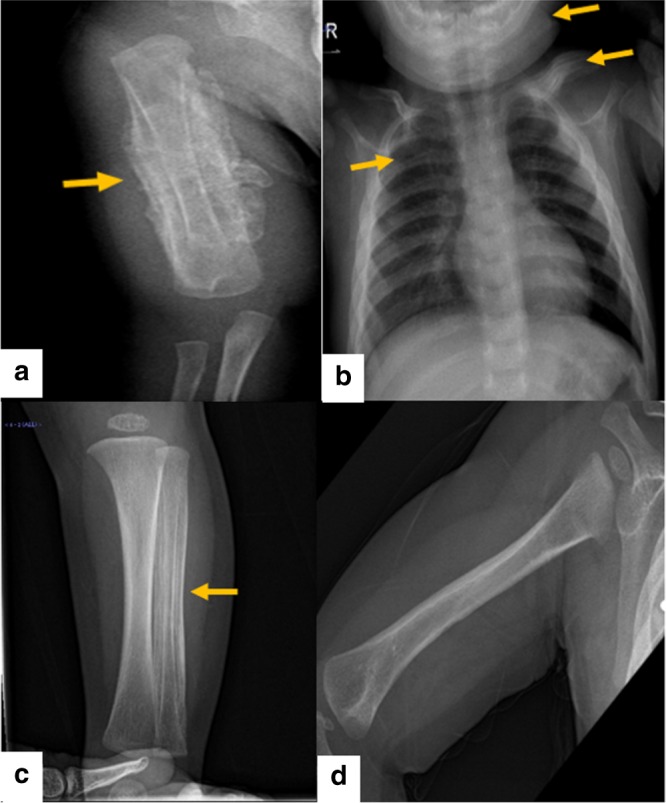

對右臂進行 X 光檢查,顯示沿右肱骨的整個骨干骨膜反應(yīng)旺盛(圖 1a)。 進一步評估包括 X 線骨骼檢查,顯示一側(cè)肩胛骨、一根腓骨、下頜骨和許多肋骨有明顯的骨膜反應(yīng)(圖 1b)。 根據(jù)臨床和放射學(xué)檢查結(jié)果,診斷為 ICH。 盡管德托尼-卡菲病可能具有短暫性,但開始使用吲哚美辛(每天 5mg/kg)治療,并且病變在幾個月內(nèi)有效消失,正如后續(xù)放射學(xué)檢查所證明的那樣(圖 1c)。 經(jīng)過 1 年的隨訪,患者有效康復(fù),沒有骨骼畸形和/或升高的炎癥標(biāo)志物。 他仍在服用低劑量的消炎痛(每天 1mg/kg)。

患者的射線照相檢查。 a 沿右肱骨整個軸的骨膜反應(yīng)。 b 沿左鎖骨、肋骨和下頜骨的骨膜反應(yīng)。 c 沿腓骨的骨膜反應(yīng)。 d 肱骨骨膜有效消退